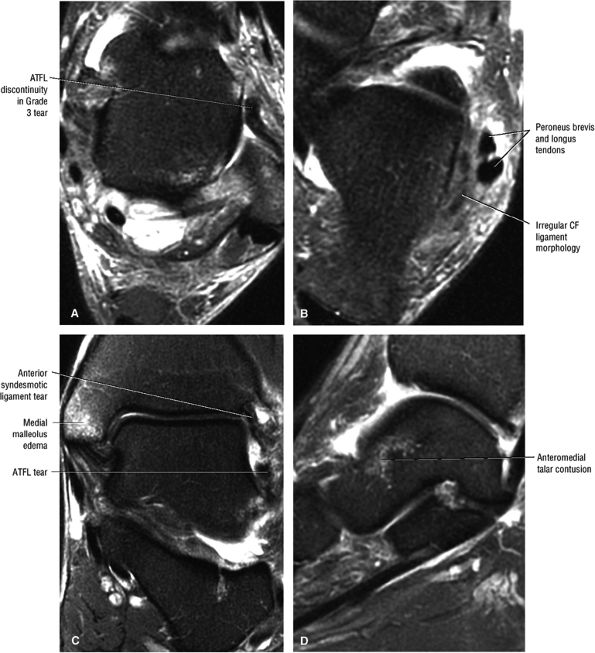

Type III: Osseous avulsion of the SPR

-

Type IV: An SPR tear posterior to the distal fibular attachment (Fig. 5.172)

![]() |

|

FIGURE 5.162 ● Peroneus brevis tendon split associated with a peroneus quartus muscle, which may contribute to mechanical crowding in the retromalleolar groove of the distal fibula. Axial PD FSE (A) and FS PD FSE (B) images.

Grade I: Stretching or partial tearing of ATFL fibers